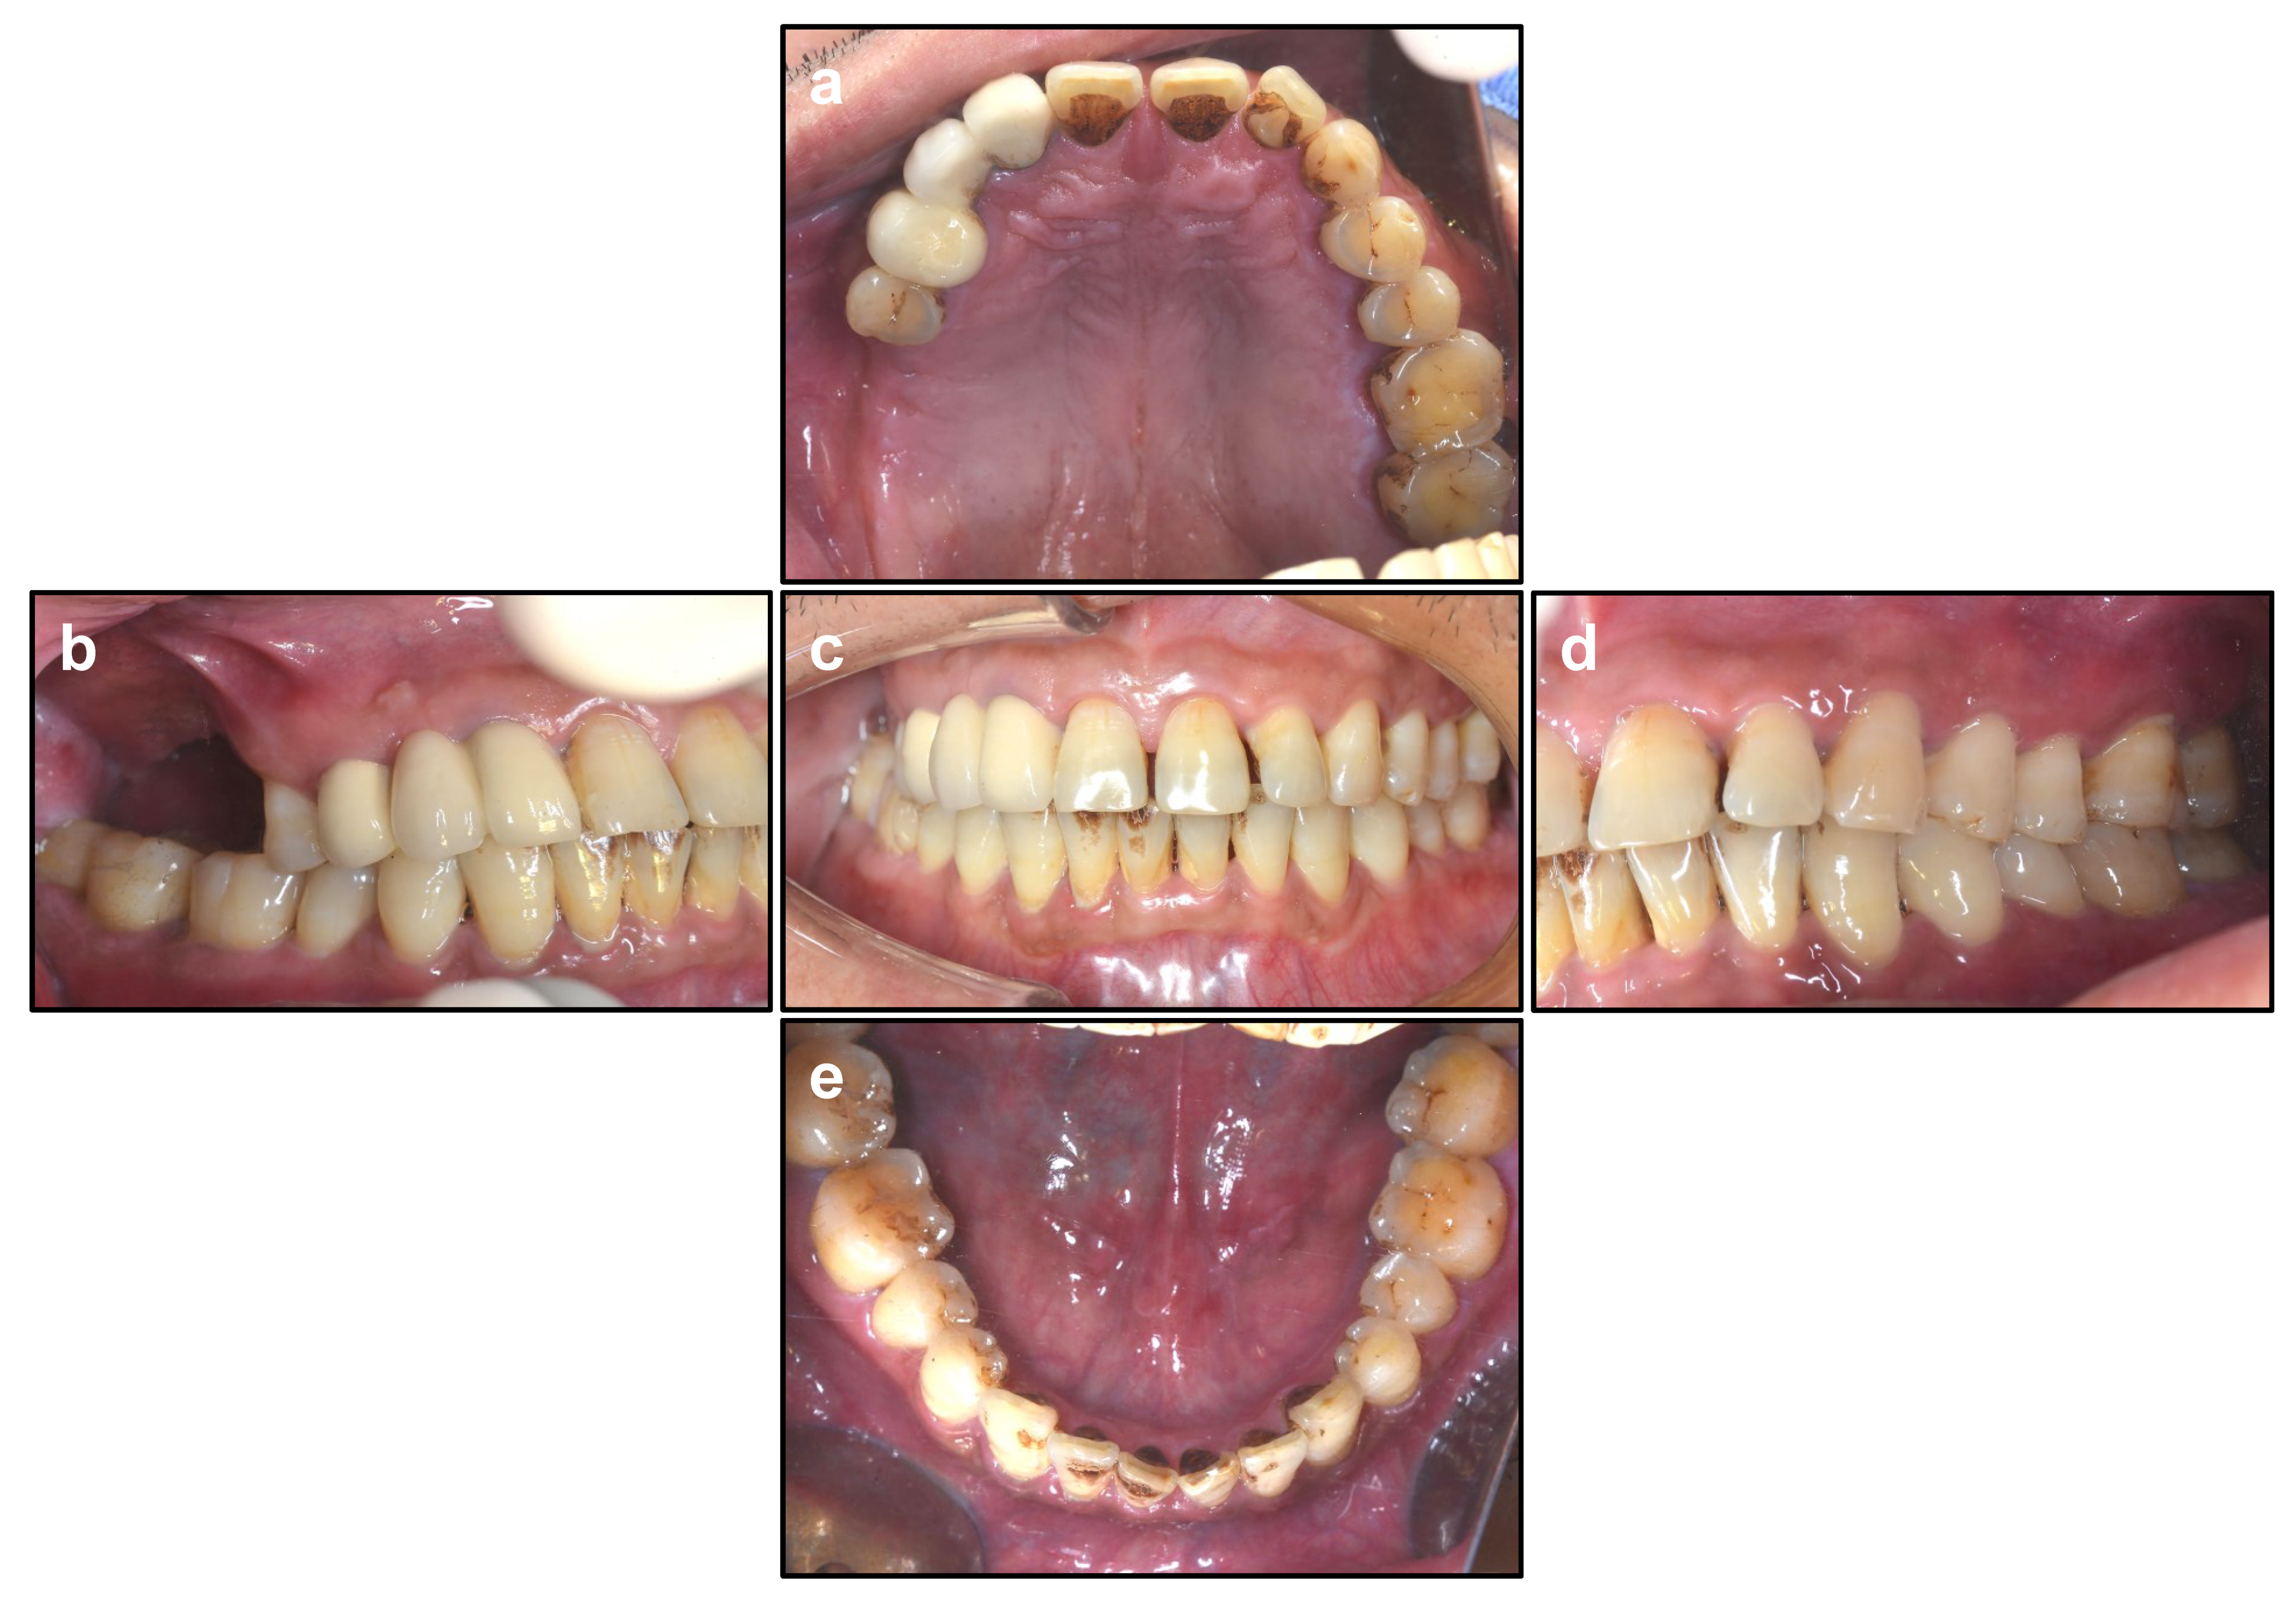

2.1. Patients’ Characteristics

2.2. Inclusion and Exclusion Criteria

- Partially edentulous patients at the maxillary posterior region, including the second premolar and first and second molar sites requiring dental implants.

- Bone width at the bony crest level sufficient to allow the insertion of regular-diameter (4.1 mm) and wide-diameter (4.8 mm) dental implants maintaining at least 1.0 mm of buccal and lingual bone. This requires at least 6–7 mm bone width at the bony crest level.